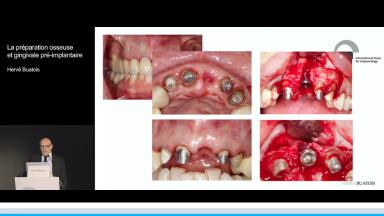

La préparation osseuse et gingivale pré-implantaire

Cette présentation expose les techniques de préparation osseuse et gingivale pré-implantaire dans les cas où les volumes osseux ne permettent pas la pose d’implant dans un axe prothétique optimal.

La pose d’un implant est un acte prothétique pouvant nécessiter une reconstruction afin d’éviter une compensation implantaire et/ou prothétique. La gestion des différents types de défauts osseux est un véritable challenge d’autant plus en secteur esthétique. Il est primordial de déterminer le niveau de difficulté d’une réhabilitation implantaire afin d’établir un pronostic et d’assurer un résultat esthétique à long terme au patient.